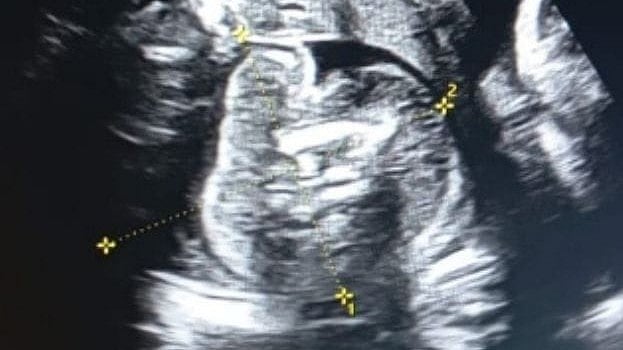

नऊ महिन्यांची गर्भवती असलेल्या महिलेच्या पोटातील गर्भाच्या पोटातही गर्भ वाढत असल्याचे नैसर्गिक आश्चर्य सोनोग्राफी तपासणी दरम्यान आढळून आले आहे. बुलढाणा जिल्हा सामान्य रुग्णालयात दोन दिवसांपूर्वी, दोन आपत्यांची माता असलेली (३२ वर्षीय) गर्भवती महिला सोनोग्राफी तपासणी करवून घेण्यासाठी आली होती. रुग्णालयातील डॉ.प्रसाद अग्रवाल यांना महिलेच्या सोनोग्राफी तपासणी दरम्यान दुर्मिळातील दुर्मिळ प्रकार दिसून आला. महिलेच्या पोटातील नऊ महिन्यांच्या गर्भाच्या पोटात आणखी एक गर्भ वाढत असल्याचे प्रथमच त्‍यांना दिसून आले. त्‍यामुळे डॉ.अग्रवाल आश्चर्यचकित झाले.

गर्भाच्या पोटात गर्भ आढळण्याचा हा प्रकार प्रसुतीबाबत गुंतागुंतीचा व जोखमीचा राहण्याची संभावना असल्याने डॉ.अग्रवाल यांनी या सोनोग्राफी रिपोर्ट बाबत जिल्हा शल्यचिकित्सक डॉ.भागवत भुसारी, शासकीय वैद्यकीय महाविद्यालयाचे अधिष्ठाता डॉ .झिने व महिला रुग्णालयाचे अधीक्षक डॉ.पाटील यांनाही अवगत केले. या वरिष्ठ वैद्यकीय तज्ञांच्या मार्गदर्शनाखाली सदर महिलेची पुन: सोनोग्राफी तपासणी करण्यात आली. नऊ महिन्याच्या गर्भाची पुर्ण वाढ झालेली आहे, मात्र त्या गर्भाच्या पोटातील गर्भाची वाढ झालेली नाही.

आज बुलढाणा येथील आमच्या यूएसजी क्लिनिकमध्ये आढळून आलेली केस ही दुर्मिळ अशी आहे. पाच लाख गर्भवती महिलांमागे अशी एक 'केस' आढळून येऊ शकते. त्याला FETUS in FeTO असे म्हटले जाते. आतापर्यंत अशा केवळ २०० केसेस नोंदवल्या गेल्या आहेत, तेही बाळंतपणानंतर (भारतात आजपर्यंत १० ते १५ केसेस नोंद झाल्या आहेत). मला गर्भवती महिलेच्या पोटातील बाळामध्ये काहीतरी असामान्य दिसून आले. तो जवळजवळ ३५ आठवड्यांचा सामान्य वाढणारा गर्भ होता. त्याच्या पोटात काही हाडे आणि गर्भासारखी रचना होती. मला लगेच लक्षात आले की हे सामान्य नाही. ही जगातील सर्वात दुर्मिळ केसेसपैकी एक आहे.